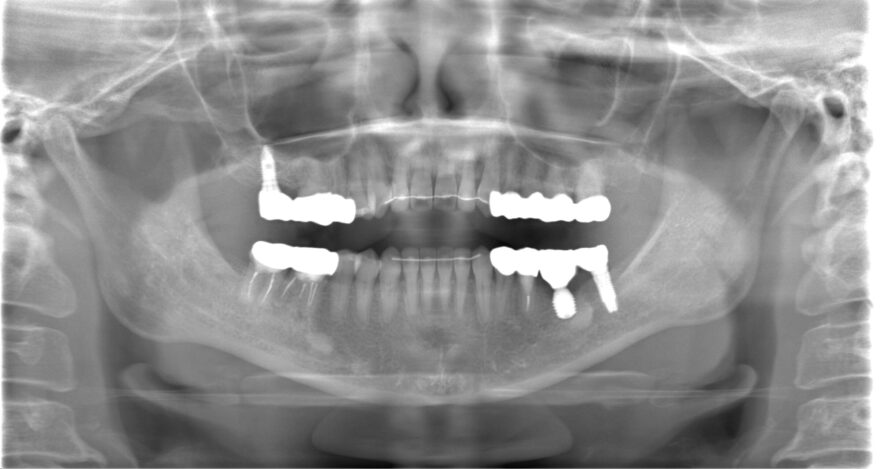

初診時のレントゲン写真

治療後のレントゲン写真